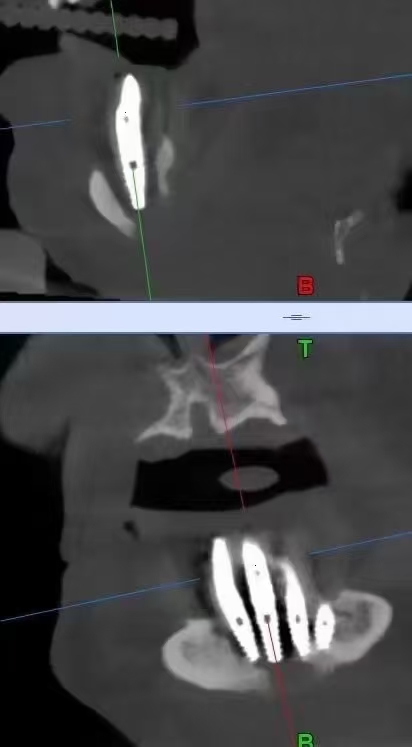

严重的种植并发症一例

严重的种植并发症

触目惊心